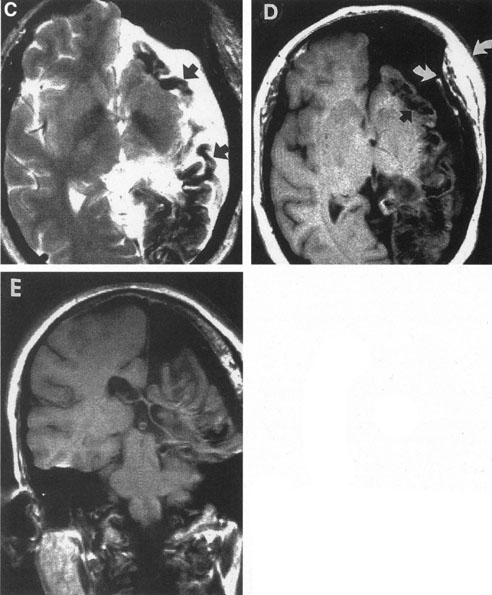

The detection of intracranial AVMs is facilitated by CT scanning and MRI (Fig. 10),88 but optimal management requires selective angiography89 that assesses the size and configuration of the mass, the number and location of feeding arteries, the flow characteristics and degree of steal from brain parenchyma, and the pattern of venous drainage.

Fig. 10. Neuroimaging of arteriovenous malformation. A: Coronal magnetic resonance imaging (MRI) (TR, 600 ms; TE, 20 ms) shows wedge-shaped vascular mass extending from the surface of the parietal cortex (white arrows) to the lateral ventricle (black arrows; asterisk, arterial feeder). B: Posteroanterior left arteriogram of the same lesion. C: Axial computed tomography scan with contrast enhancement. D: Axial MRI of a large arteriovenous malformation, first echo (TR, 2000 ms; TE, 20 ms). E: Second echo (TR, 2000 ms; TE, 90 ms). (From Smith HJ, Strother CM, Kikuchi Y, et al: MR imaging in the management of supratentorial intracranial AVMS. AJNR Am J Neuroradiol 9:225, 1988.)